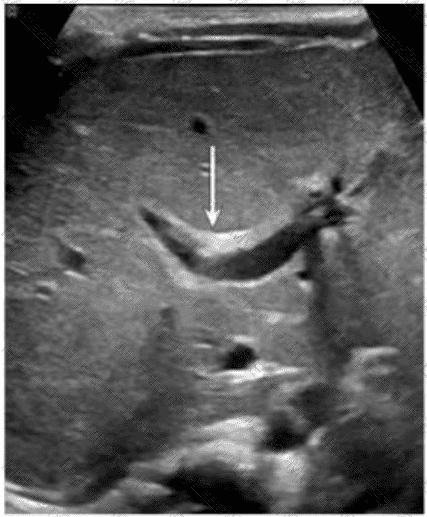

Which congenital disorder is most consistent with the finding identified by the arrow on this image?